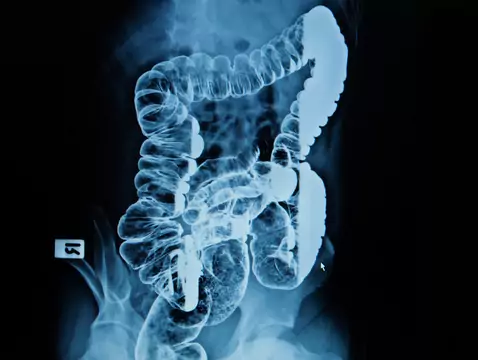

Rak jelita grubego to zwykle gruczolakorak. Częściej występuje u mężczyzn niż u kobiet. Rzadko stwierdza się go przed 40. rokiem życia – lecz ostatnie lata pokazały, że na ten rodzaj nowotworu...

Rak jelita grubego stanowi drugi co do częstości występowania nowotwór złośliwy Polaków. Zachorowalność stale wzrasta, a wiek zachorowań maleje. Ma to związek z coraz bardziej rozpowszechnionymi...